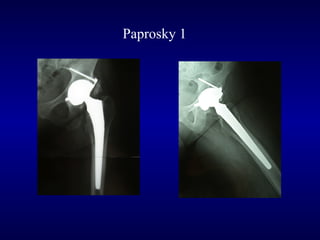

Paprosky 1

Follow up a 3

anni

Post-op

F.U. 6 anni